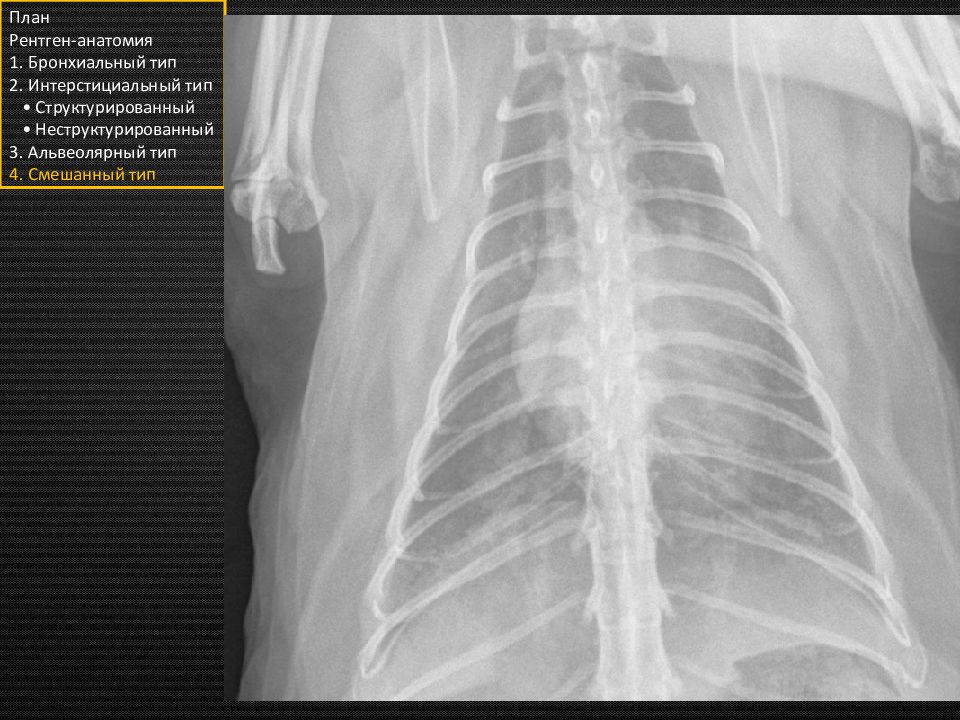

Слайд 6

Прямая проекция План Рентген-анатомия 1. Бронхиальный тип 2. Интерстициальный тип • Структурированный • Неструктурированный 3. Альвеолярный тип 4. Смешанный тип